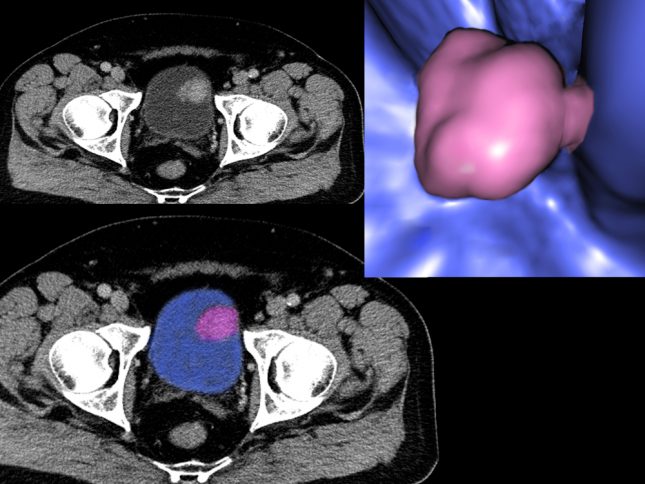

סרטן שלפוחית השתן